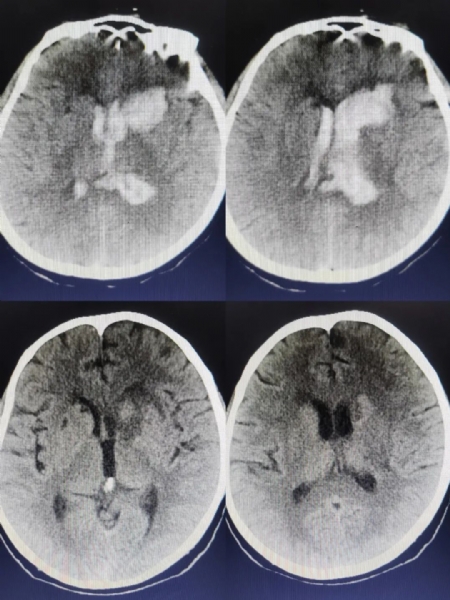

2023年1月22日凌晨,正值农历新年第一天,张大姨在家中突发剧烈头痛、头晕伴恶心、呕吐,家人紧急送到我院就诊,来院时已处于昏迷状态,血压高达270/110mmHg。急诊科医师紧急进行降压处理、开具颅脑CT,并请外二科会诊。经相关检查,确诊为脑内出血并破入脑室,病情十分危急,需及时进行手术处理。当晚,外二科值班医师季鑫对张大姨进行全面评估后,告知家人病情。取得家人同意后,第一时间联系相关科室,准备手术。